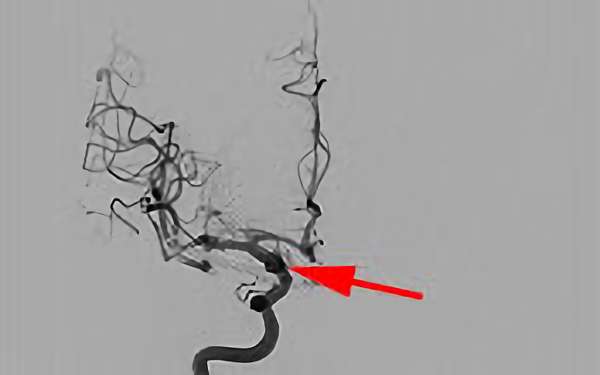

No.1617 手術後